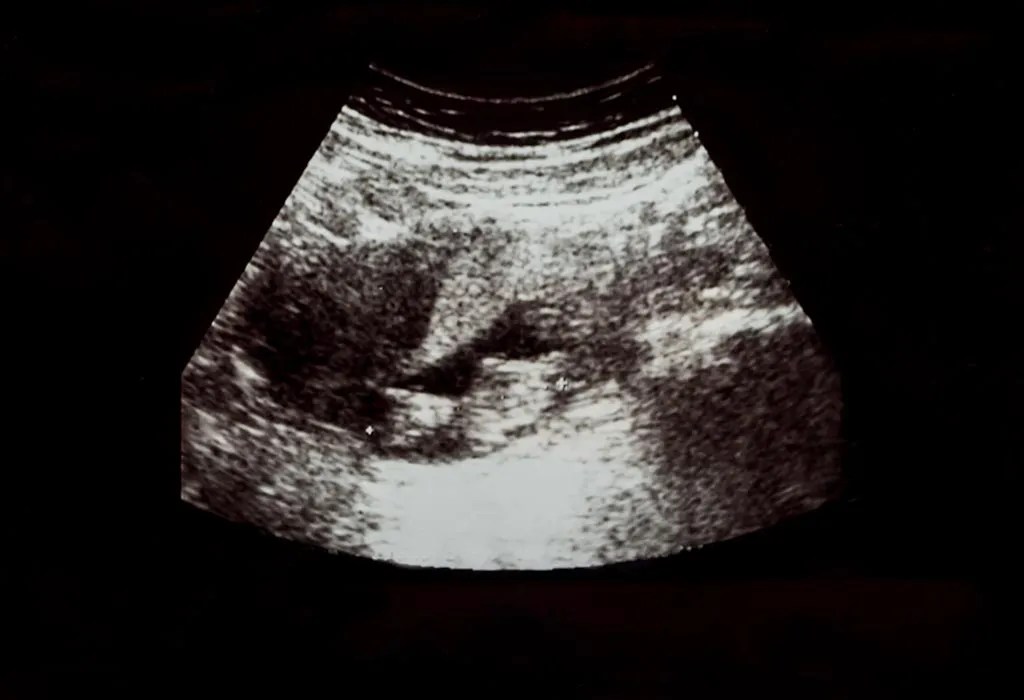

A monochorionic, diamniotic gestation can have the presence of a "t" sign, which is the appearance of the amnion as it comes off the placenta at . Lambda sign for dichorionic pregnancy; See also · t sign: Two yolk sacs (this won't tell whether it's a mo/di or a di/di pregnancy though!). Twin reversed arterial perfusion (trap sequence) is a rare condition of monochorionic twin pregnancies. As in singletons, impaired fetal growth can be assessed in twins by. Single gestational sac or t sign . 8) 32year old g2p1 at 20 weeks pregnancy in usg shows twin pregnancy, single placental mass with dividing membrane having inverted t sign.

A monochorionic, diamniotic gestation can have the presence of a "t" sign, which is the appearance of the amnion as it comes off the placenta at .

8) 32year old g2p1 at 20 weeks pregnancy in usg shows twin pregnancy, single placental mass with dividing membrane having inverted t sign t sign in twin pregnancy. Dence suggests an inverse relationship between gestational.